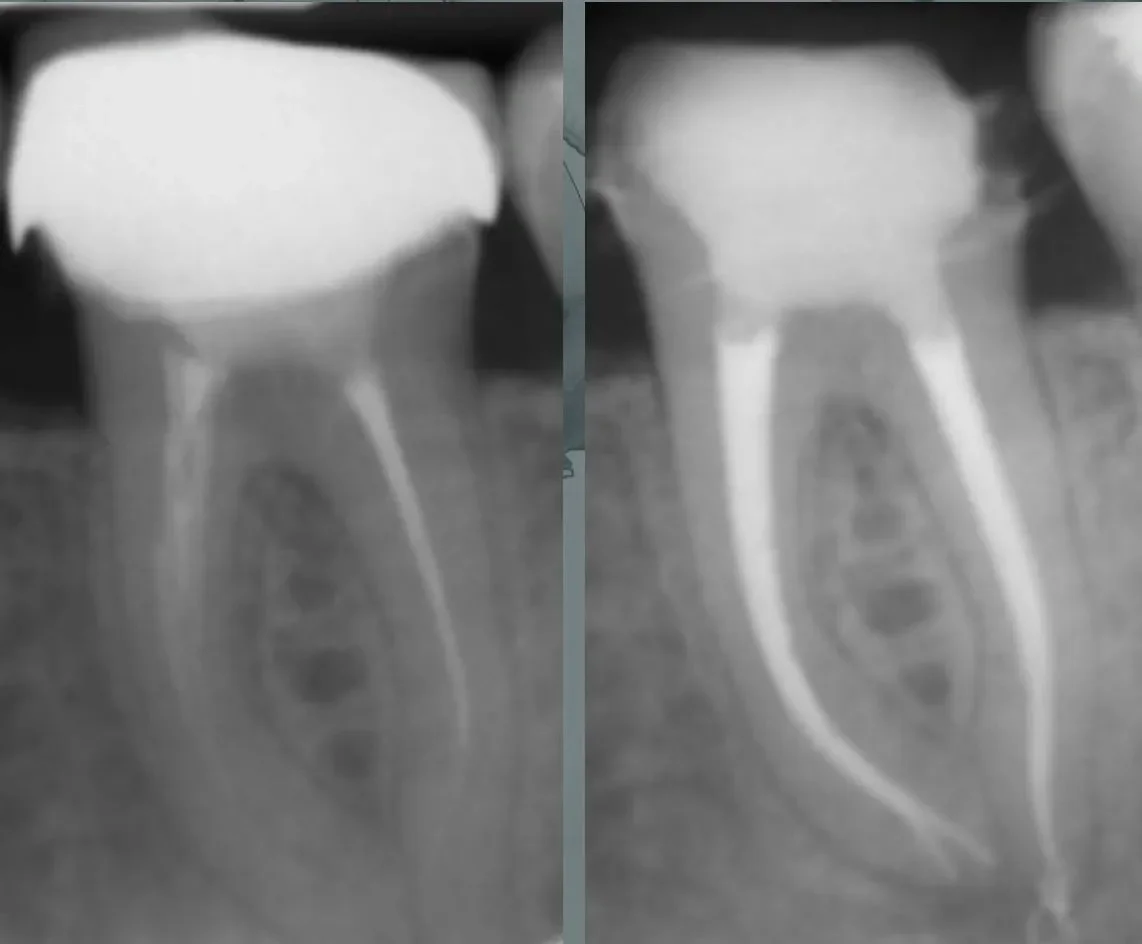

Obturation Techniques

- Principles of obturation and various materials

- Warm and cold obturation methods

- Practice using warm and cold obturation methods

- Evaluating different obturation materials for optimal results